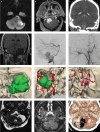

Introduction Skull base neuroanatomy is classically taught using surgical atlases. Although these texts are critical and rich resources for learning three-dimensional (3D) relationships between key structures, we believe they could be optimized and complemented with step-by-step anatomical dissections to fully meet the learning needs of trainees. Methods Six sides of three formalin-fixed latex-injected specimens were dissected under microscopic magnification. A far lateral craniotomy was performed by each of three neurosurgery resident/fellow at varying stages of training. The study objective was the completion and photodocumentation of the craniotomy to accompany a stepwise description of the exposure to provide a comprehensive, intelligible, and anatomically oriented resource for trainees at any level. Illustrative case examples were prepared to supplement approach dissections. Results The far lateral approach provides a wide and versatile corridor for posterior fossa operation, with access spanning the entire cerebellopontine angle (CPA), foramen magnum, and upper cervical region. Key Steps Include The study includes the following steps: positioning and skin incision, myocutaneous flap, placement of burr holes and sigmoid trough, fashioning of the craniotomy bone flap, bilateral C1 laminectomy, occipital condyle/jugular tubercle drilling, and dural opening. Conclusion Although more cumbersome than the retrosigmoid approach, a far lateral craniotomy offers unparalleled access to lesions centered lower or more medially in the CPA, as well as those with significant extension into the clival or foramen magnum regions. Dissection-based neuroanatomic guides to operative approaches provide a unique and rich resource for trainees to comprehend, prepare for, practice, and perform complex cranial operations, such as the far lateral craniotomy.